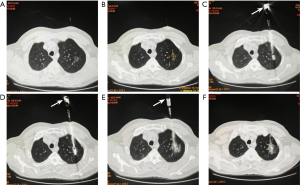

All procedures were performed by physicians with more than 5 years of experience in thermal ablation. Oxygen saturation, blood pressure, and heart rate were conducted during the procedure. The operation flow of the representative case of group A is shown in Figure 2.

- Step 1: a large-aperture spiral computed tomography (CT) was used as the interventional guidance device (GE Discovery 16 Slice CT, GE Healthcare, Chicago, USA), a low-dose scan was performed, and the PNs were reconstructed using a 1-mm thickness. Depending on the location of the lesion, it was decided that the patient would be placed in a flat, prone, or lateral position. After placing the localizer, a CT scan was performed to determine the optimal level of puncture, determine the angle of puncture and the depth of needle entry, and design the puncture route.

- Step 2: the selected puncture site was sterilized and prepared in a sterile manner. Local anesthesia with 2% lidocaine (5–10 mL) was administered at the selected puncture site.

- Step 3: a 17-G coaxial puncture needle (Canyon Medical Inc., Nanjing, China) was threaded to the proximal edge of the PNs after local anesthesia. After removing the needle, the 18-G MWA antenna (KY-2450B-T2/1.3 mm, Canyon Medical Inc.) was passed through the 17-G cannula (Canyon Medical Inc.) to penetrate the lesion. Another CT scan was performed to determine that the tip of the MWA antenna was located at the distal edge of the nodule. The ablation power was 35–40 W, and the ablation time was 4–8 min. Immediately after the end of the MWA, a CT scan of the chest was performed.

- Step 4: after the end of MWA, the ablation antenna was withdrawn, and an 18-G biopsy gun (Canyon Medical Inc.) was inserted through the cannula along the same needle pathway. Then sampling is performed, and the operator usually performs 1–3 samplings to obtain sufficient pathological specimens. The obtained tissue specimens are fixed in formalin solution and sent to the pathology department for pathological examination. A CT examination was routinely performed after PB to observe whether there were any immediate complications.

- Step 5: all specimens were sent to the pathology department to determine the final pathological diagnosis. Hematoxylin-eosin (H&E) staining, immunohistochemical staining and genetic testing were performed on biopsy specimens. The quality of genetic testing specimens was assessed, and the quality control criteria were ≥30 ng of total DNA extraction, ≥1,000× average sequencing depth, ≥95% of sequence replication/coverage, and ≥80% of base quality Q30 (immunostaining was added according to the judgment of the pathologist. Decide whether or not to perform genetic testing based on the pathologic results combined with the patient’s request).

- Step 6: after the end of ablation, gelatin sponge particles (1,400–2,000 µm) were pushed through the coaxial cannula with 2 mL of 50% dextrose injection mixture to seal the puncture channel to reduce the risk of pneumothorax in patients, and then the needle was removed.

- Step 7: after the end of treatment, perform a CT examination to observe the ablation range and observe whether the patient has pneumothorax, intrapulmonary hemorrhage, and other serious complications.